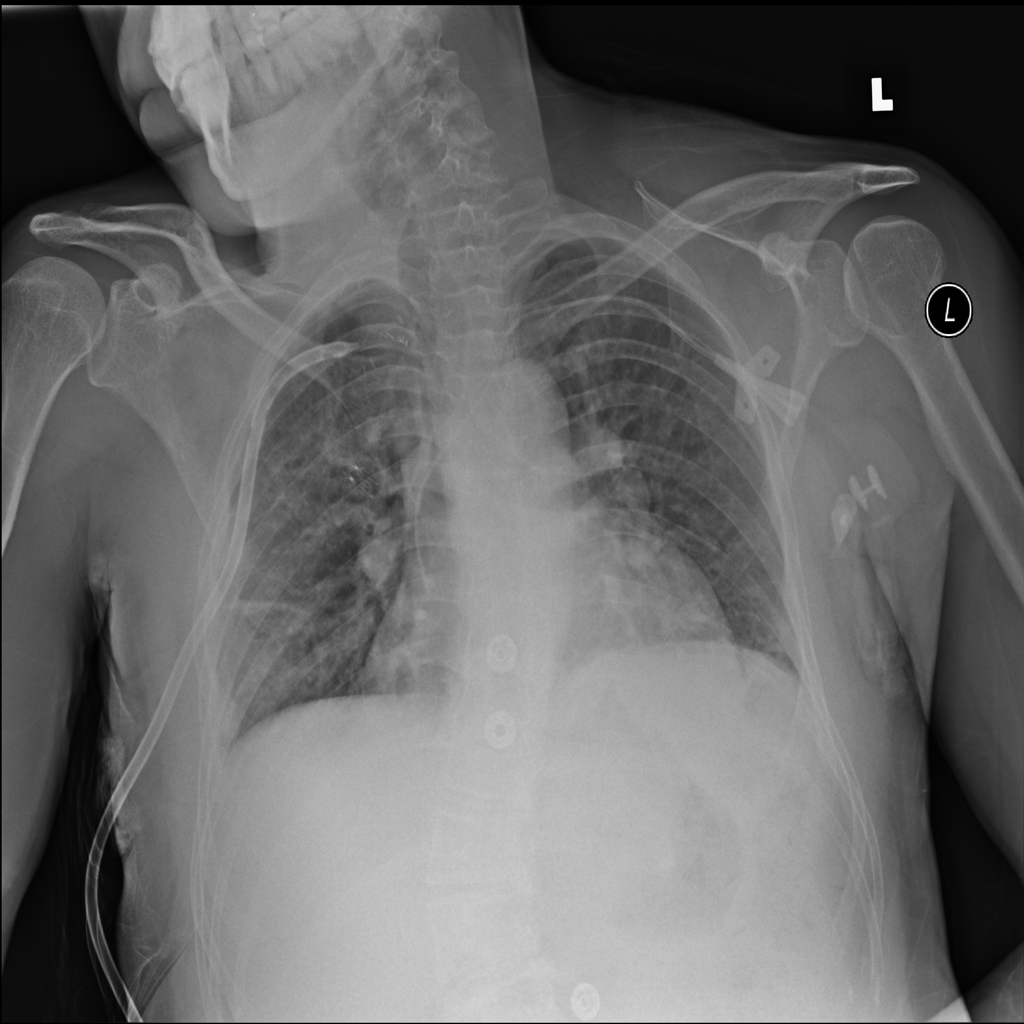

PAT-DB80 · IMG-001Atelectasis

PAT-DB80 · IMG-001

PA